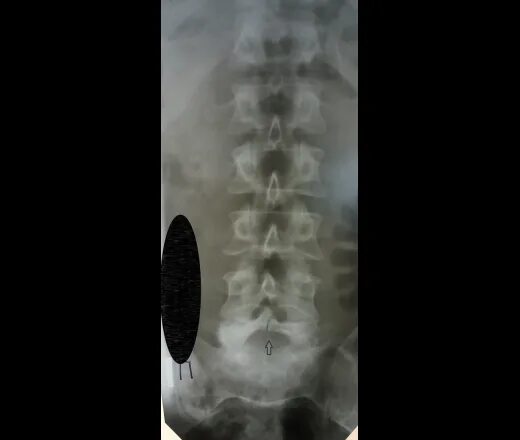

Незаращение дужки позвонка